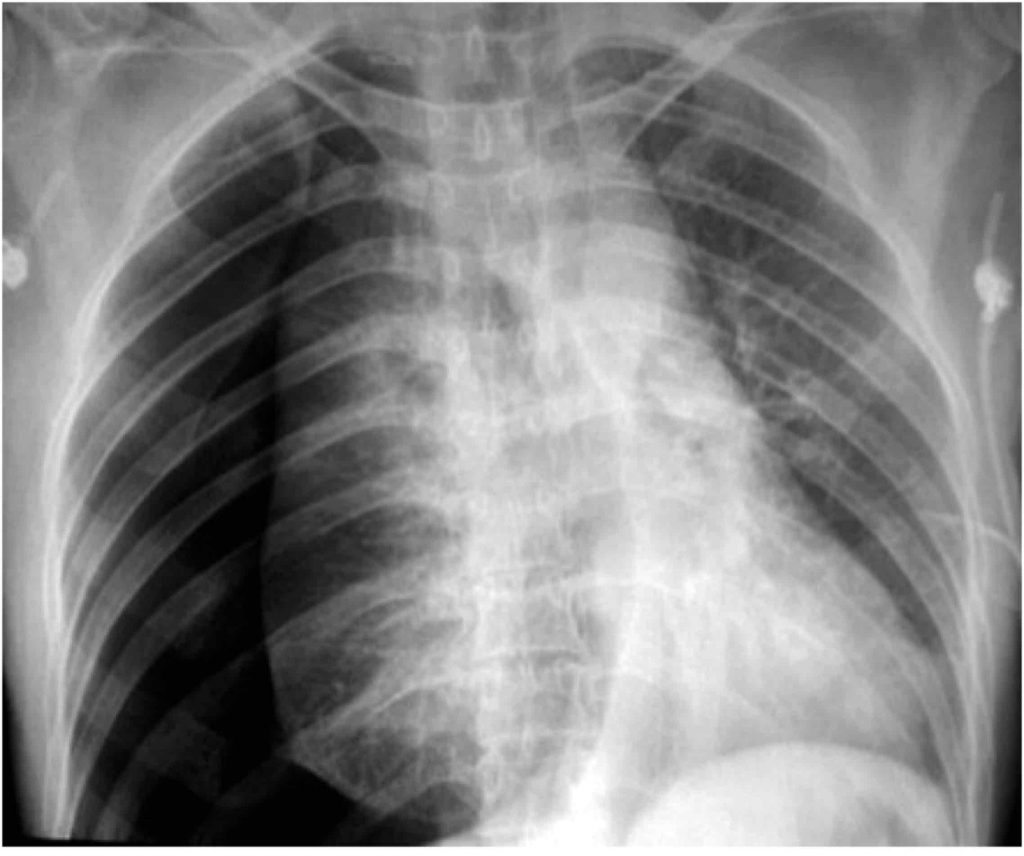

Along with the diaphragm, the clinician should also be making note of the costophrenic angles. They should be sharp bilaterally and are formed from the dome of each hemidiaphragm and lateral chest wall. The loss of a costophrenic angle (blunting) also often indicates the presence of fluid or consolidation. There can also be flattening of the diaphragms with costophrenic blunting. This alone with hyperinflation (think back to R.I.P) is an indicator of emphysematous changes (COPD). In the two images above note the hyperinflation, blunting of the costophrenic angles and especially the flattened diaphragms. This is a very ‘classic’ example of COPD: